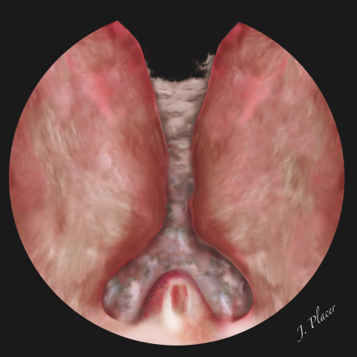

El siguiente paso consiste en la realización de una incisión desde el cuello de la vejiga hasta la incisión transversa realizada previamente a la altura del borde superior del verumontanum (Figura 5). Esta incisión debe irse profundizando de forma progresiva y uniforme a través del adenoma hasta llegar al plano de la cápsula quirúrgica de la próstata. La cápsula prostática no tiene el mismo grosor ni se visualiza de igual manera en toda su superficie. A nivel del cuello de la vejiga se observa como la existencia de fibras blanquecinas dispuestas en sentido transversal o circular. En ocasiones no se sabe que se ha alcanzado el plano de la cápsula hasta que no se identifica una fina capa fibrosa a través de la cual se adivina por trasparencia la existencia de grasa en profundidad. Como la energía del láser holmio no carboniza ni altera el aspecto de los tejidos, la imagen que tiene el adenoma seccionado y la cápsula prostática es algo diferente a la imagen que se observa durante la realización de una RTU-P. Uno de los errores que se suele cometer en este paso, sobre todo durante la enucleación de próstatas con gran crecimiento retrotrigonal, consiste en la realización de un escalón subcervical o incluso subtrigonal. Para evitarlo es importante que la incisión practicada desde el cuello de la vejiga hasta el verumontanum sea una única línea recta que no tenga escalones ni serpentee. Tras la realización de la incisión es muy importante su ampliación en ambos sentidos hacia ambos lóbulos laterales a fin de que la incisión se convierta en un amplio canal. Cuando no se dispone de experiencia se suelen realizar múltiples trayectos que discurren de forma paralela y a diferente nivel de penetración en el adenoma en vez de una única incisión que llega a la cápsula prostática, ocasionado la pérdida de orientación y tiempo.

Figura 5. Incisión practicada desde el cuello de la vejiga hasta el verumontanum. La incisión se realiza a nivel de las 5, 6 o 7 horarias en función de la anatomía de la glándula (próstata bilobulada o trilobulada) y se extiende hacia ambos lóbulos laterales para crear un amplio canal

El lugar en el que practicamos la incisión desde el cuello de la vejiga hasta el verumontanum depende de la anatomía de la glándula prostática. La presencia o ausencia de un lóbulo medio megálico así como su tamaño determina si hacemos una o varias incisiones entre el cuello y el verumontanum. Así, cuando la próstata presenta dos lóbulos laterales prominentes pero no tiene lóbulo medio (próstata bilobulada), solemos realizar la incisión en la línea media a nivel de las 6 horarias y posteriormente la ampliamos lateralmente hacia ambos lóbulos laterales. En cambio, cuando además hay un lóbulo medio (próstata trilobulada) que no es muy grande preferimos practicar la incisión a nivel de las 7 horarias. El objetivo es enuclear por un lado el lóbulo medio junto con el lóbulo lateral izquierdo y por otro lado el lóbulo lateral derecho. Adoptando cualquiera de las dos estrategias es muy importante que tras realizar la incisión y alcanzar el plano de la cápsula prostática, la disección se extienda hacia derecha e izquierda. De esta manera el surco creado se transforma en un amplio canal que facilita la visión endoscópica y la posterior disección de los lóbulos laterales.